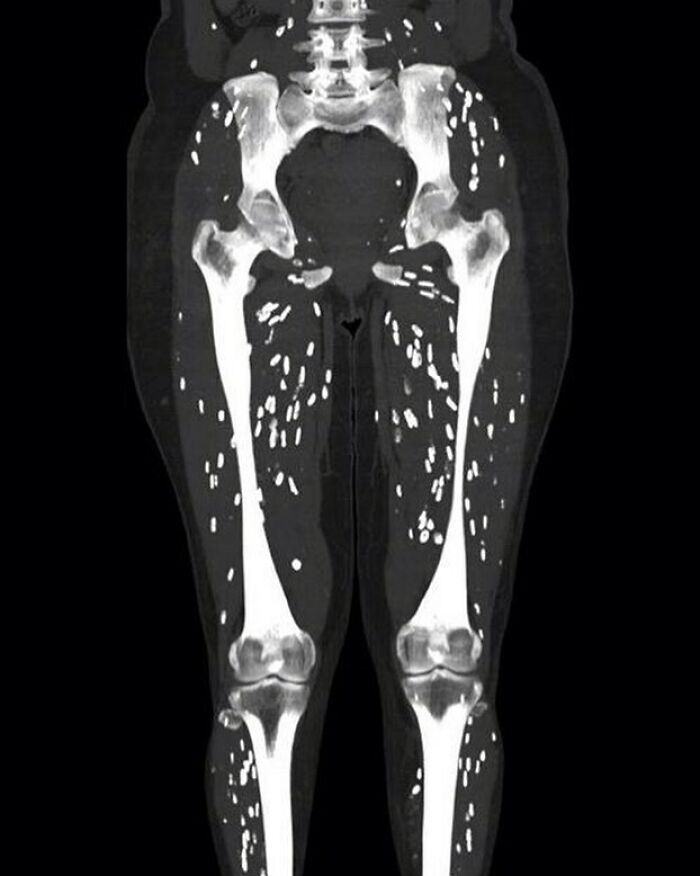

#74

The picture shows oblong calcific specks in the skeletal muscles parallel to the muscle fibres (rice-grain calcification) consistent with musculoskeletal cysticercosis. The calcifications parallel the long axis of the muscle. This is characteristic of infection with Taenia solium (cysticercosis)